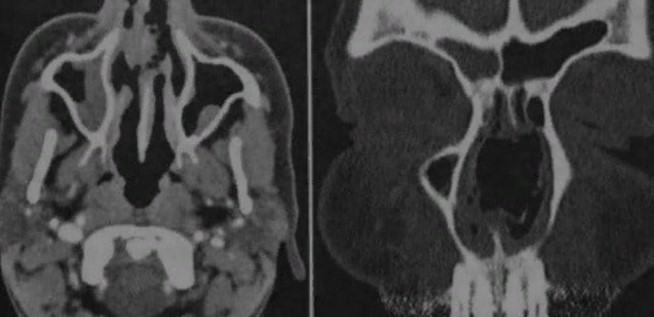

КТ-снимки хронического этмоидита: подробная визуализация